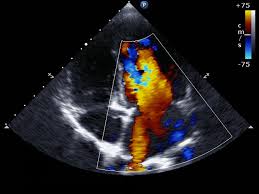

Doppler echocardiogram: In addition to sound waves bouncing off the solid structures of the heart, they also bounce off the red blood cells as they circulate through the heart chambers. Using Doppler technology, the echocardiogram can assess the speed and direction of blood flow, helping increase the amount and quality of information available from the test. The computer can add color to help the doctor appreciate that information. Color flow Doppler is routinely added to all echocardiogram studies and is the same technology used in weather reports.